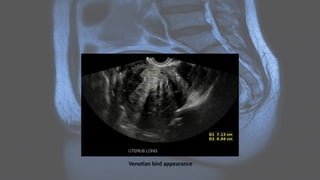

• Venetian blind artifact may be seen but edge shadowing +/- dense posterior

shadowing from calcification is also typically seen 17

Venetian bird appearance

• A "Venetian blind" or "rain shower" appearance (linear striations,

parallel shadowing) may be seen as a combination of the

aforementioned features: heterogeneous 1,2,20, coarsened

echotexture of the myometrium, and acoustic shadowing where

endometrial tissues cause a hyperplastic reaction. The combination of

this heterogeneity and the subendometrial echogenic nodular and

linear striations is not dissimilar to the appearance of chronic liver

parenchymal disease - hence, “cirrhosis of the uterus.”

Ultrasound • Ultrasound isused to diagnose the presence and monitor the growth of fibroids: • uncomplicated leiomyomas are usually hypoechoic, but can be isoechoic, or even hyperechoic compared to normal myometrium • calcification is seen as echogenic foci with shadowing • cystic areas of necrosis or degeneration may be seen • Venetian blind artifact may be seen but edge shadowing +/- dense posterior shadowing from calcification is also typically seen 17

USG • A "Venetianblind" or "rain shower" appearance (linear striations, parallel shadowing) may be seen as a combination of the aforementioned features: heterogeneous 1,2,20, coarsened echotexture of the myometrium, and acoustic shadowing where endometrial tissues cause a hyperplastic reaction. The combination of this heterogeneity and the subendometrial echogenic nodular and linear striations is not dissimilar to the appearance of chronic liver parenchymal disease - hence, “cirrhosis of the uterus.”